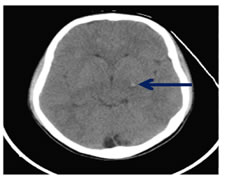

Diffuse axonal injury (DAI) is the Disruption of the cytoskeletal network and axonal membranes. Axonal damage occurs with axonal rotational acceleration and deceleration movementdue to traumatic effect21 DAI is also known as "shearing injury". Diffuse axonal injury typically consists of several focal white-matter lesions measuring 1-15 mm in a characteristic distribution. 6 Traumatic micro-bleeds are considered to be a radiologic marker for DAI 20,21 Location of DAI are typical, Subcortical and deep white matter are commonly affected. Cortex will be spared. DAI locates in subcortical white matter (mild form), corpus callosum (middle form) andbrainstem (severe form).21 On CT initially often normal. Subcortical white matter, corpus callosum or brain stem may show small hypodense foci which are corresponding to edema of shearing injury. Punctatehemorrhagic lesions may appear as hyperdense foci on CT. (Fig 11) MRI (Fig 12) Magnetic resonance imaging (MRI) is the preferred examination for DAI (particularly with gradient-echo sequences. T2W- image shows multifocal hyperintense lesions at characteristic locations. Especially, hemorrhagic lesions are seen as blooming in SWI sequence. Multifocal hypointense foci on SWI are seen due to susceptibility of blood products.20,21,22

Figure 11: Axial NECT scan: A 15-year old boy was presented after a motorcycle accident showing hemorrhagic (arrow) DAI in left basal ganglia.